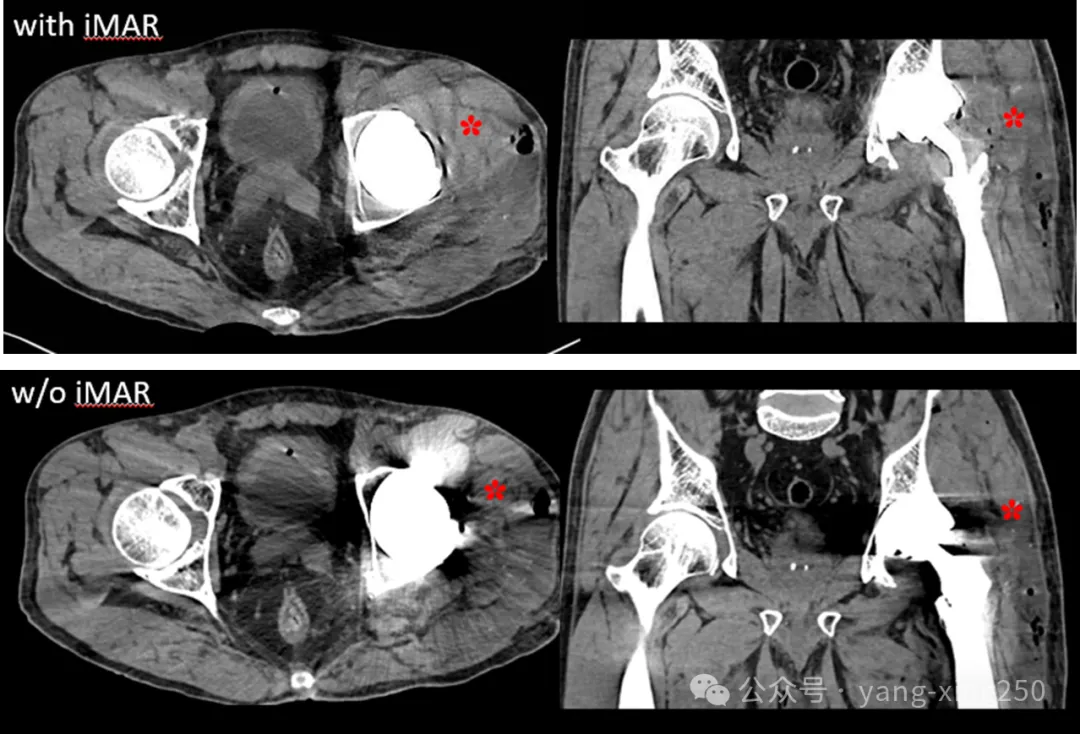

1、iMAR(iterative Metal Artifact Reduction)

原理:iMAR是通过射线束硬化矫正、线性内插值以及自适应正弦图修复和分频去金属伪影等多种迭代计算,可以明显减少图像中的条状伪影,并同时校正受影响的组织CT值,使之更接近于无金属情况下的真实值。

优缺点:在不增加辐射剂量的同时,可回顾重复使用原始数据重建,但是,对产生的严重金属伪影去除效果不理想。iMAR主要应用在光子饥饿效应引起的伪影,如人工金属髋关节置换。

也有研究表明,iMAR+双能量去金属伪影效果最佳;其次依次为双能量、iMAR。如下图: